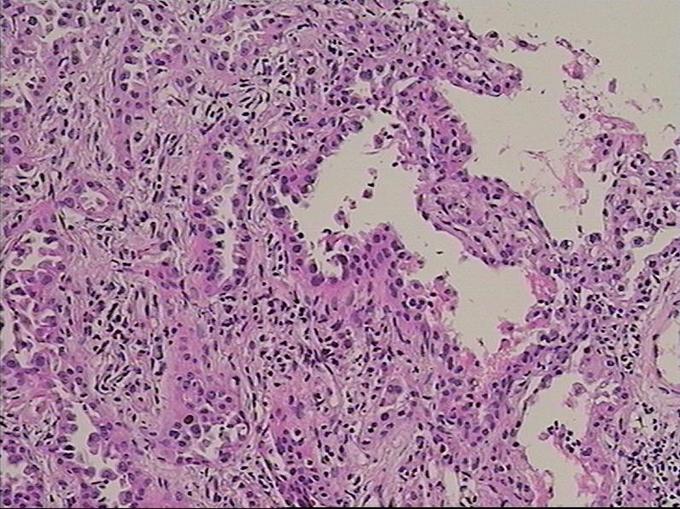

诊断为右肺上叶前段,下叶背段高分化腺癌,T4N0M0(IIIA)期 行胸腔镜手术楔形切除术,术后测EGFR阳性,给予分子靶向药物埃克替尼治疗

患者无任何症状,体检发现肺部小结节影,观察2月,未见缩小,似有轻度增大,入院后经CT引导下肺穿刺活检提示高分化腺癌,行手术治疗。 周围型肺癌早期影像学表现为孤立的肺内结节或肿块,通常有分叶征,毛刺征,空泡征,支气管充气征,坏死液化或空洞形成。此患者仅表现为淡薄的渗出影,小结节影,观察2月没有变化后,经穿刺证实肺癌,因此对肺部小结节影,斑片影,不吸收,无钙化的要特别注意肿瘤可能。